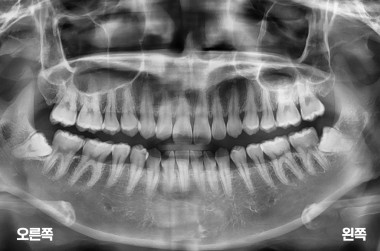

사랑니 4개 발치

MORE